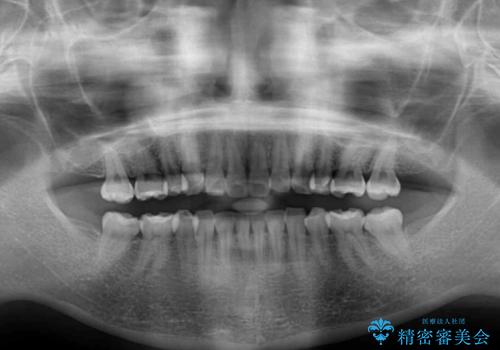

デコボコが解消されるのはもちろんのこと、突出感のあった前歯を引っ込めることができ、患者様には大変満足していただきました。

- 1年2ヶ月